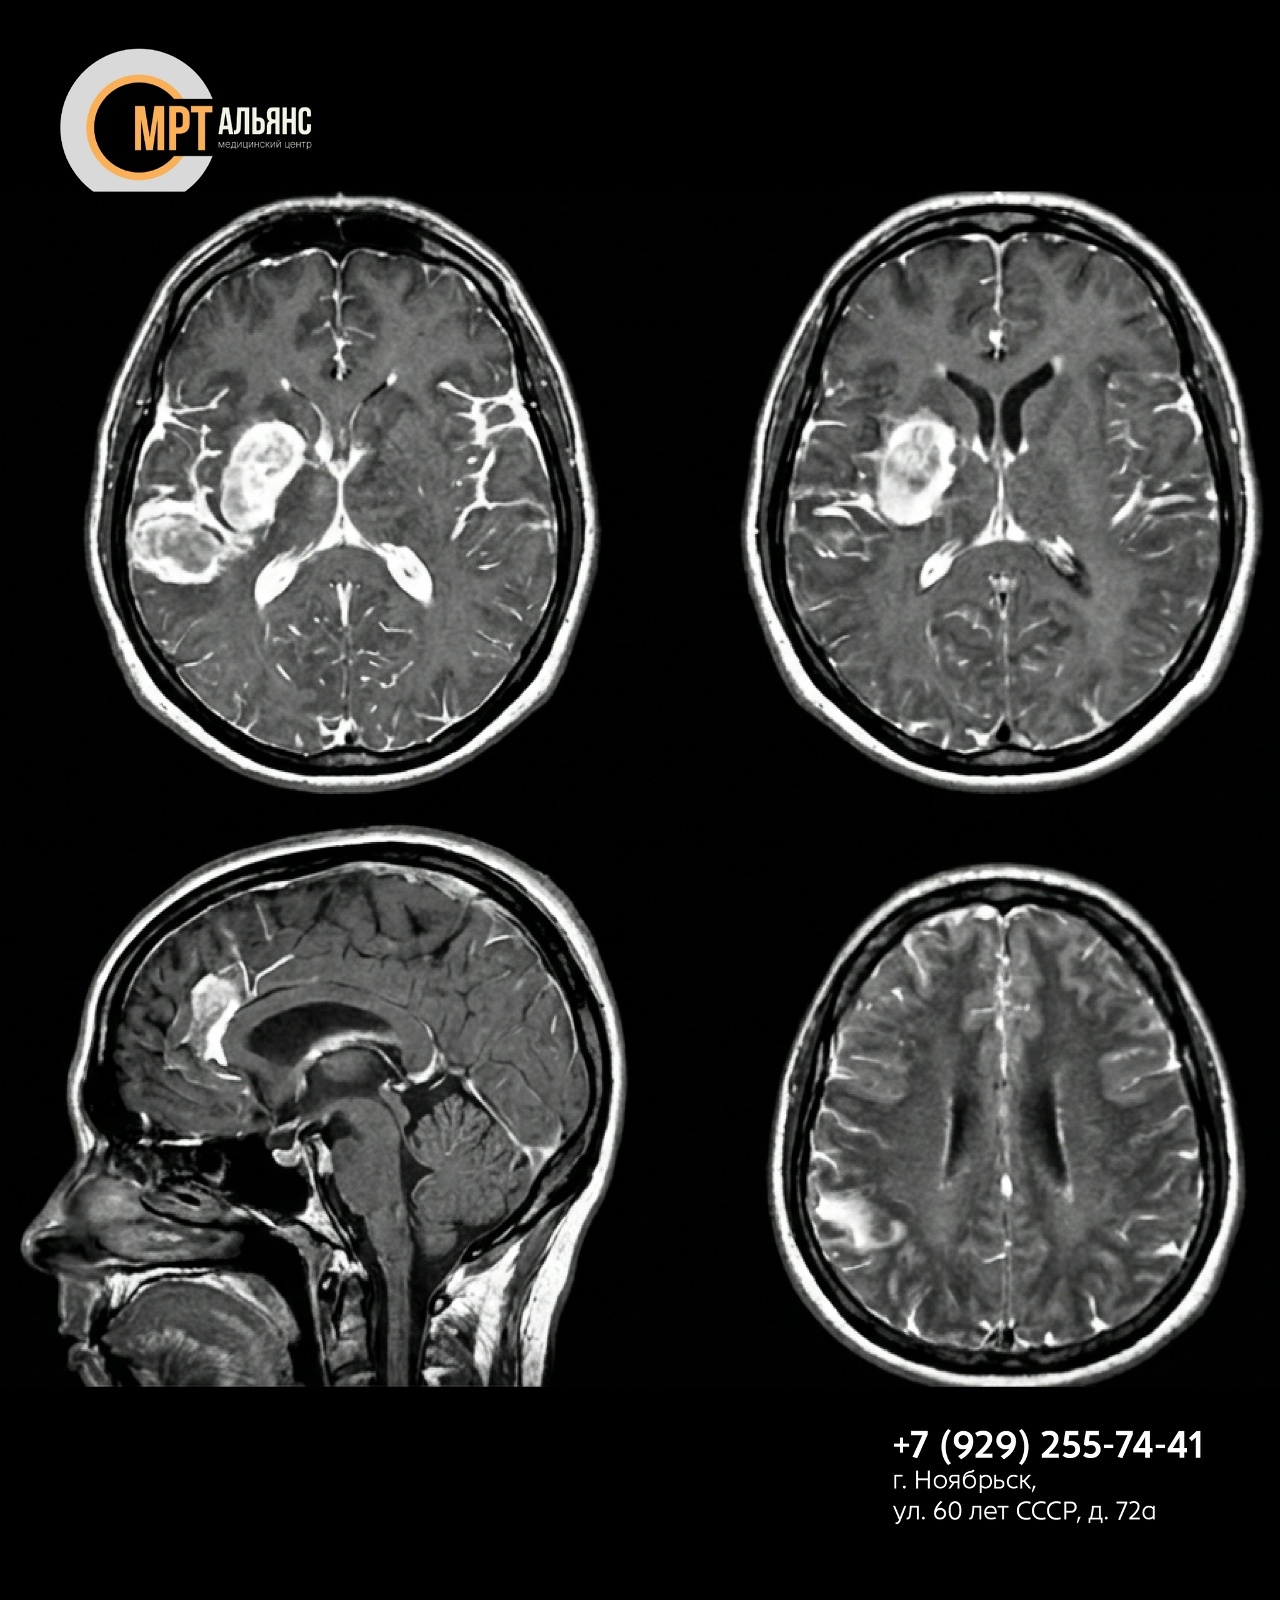

— Очаги патологической неоваскуляризации (опухоли, метастазы)

— Активные воспалительные изменения (демиелинизирующие бляшки при рассеянном склерозе)

— Нарушения гематоэнцефалического барьера

— Микроаневризмы и сосудистые мальформации